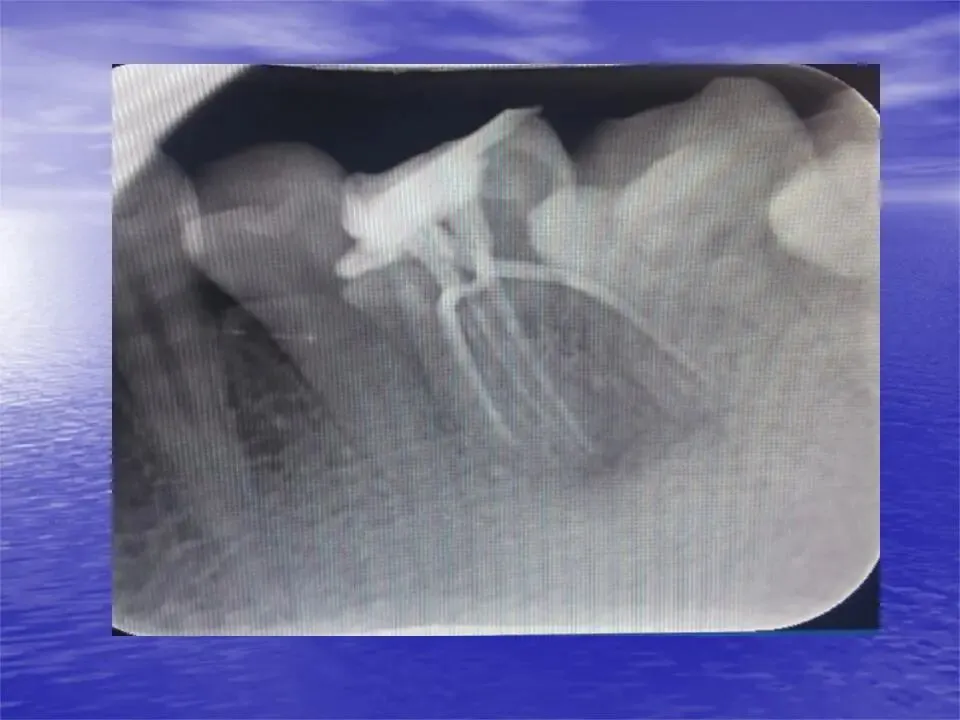

④ 机械预备后,最终冲洗的冲洗液量应大于5 mL/根管。存在感染的根管建议至少预备至30#,以便30#冲洗针能够达到足够深度,确保冲洗液在根尖1/3区域的有效作用,清除根尖区域牙髓组织、碎屑和感染物质。

最终冲洗的顺序如下 :NaClO(2.50%~5.25%)冲洗1分钟→EDTA(17%)冲洗1分钟→重新注入NaClO 30秒。为了确保冲洗液渗透到根管中,冲洗液可以通过动能冲洗激活,如超声波、声波、激光、负压冲洗或机械搅拌。

在每个根管中冲洗液冲洗三次,在冲洗液充满髓腔和根管系统的情况下进行超声波冲洗20秒,持续1分钟,以增加化学刺激物的作用。注意在两种不同冲洗液之间使用生理盐水冲洗,避免冲洗液相互反应。